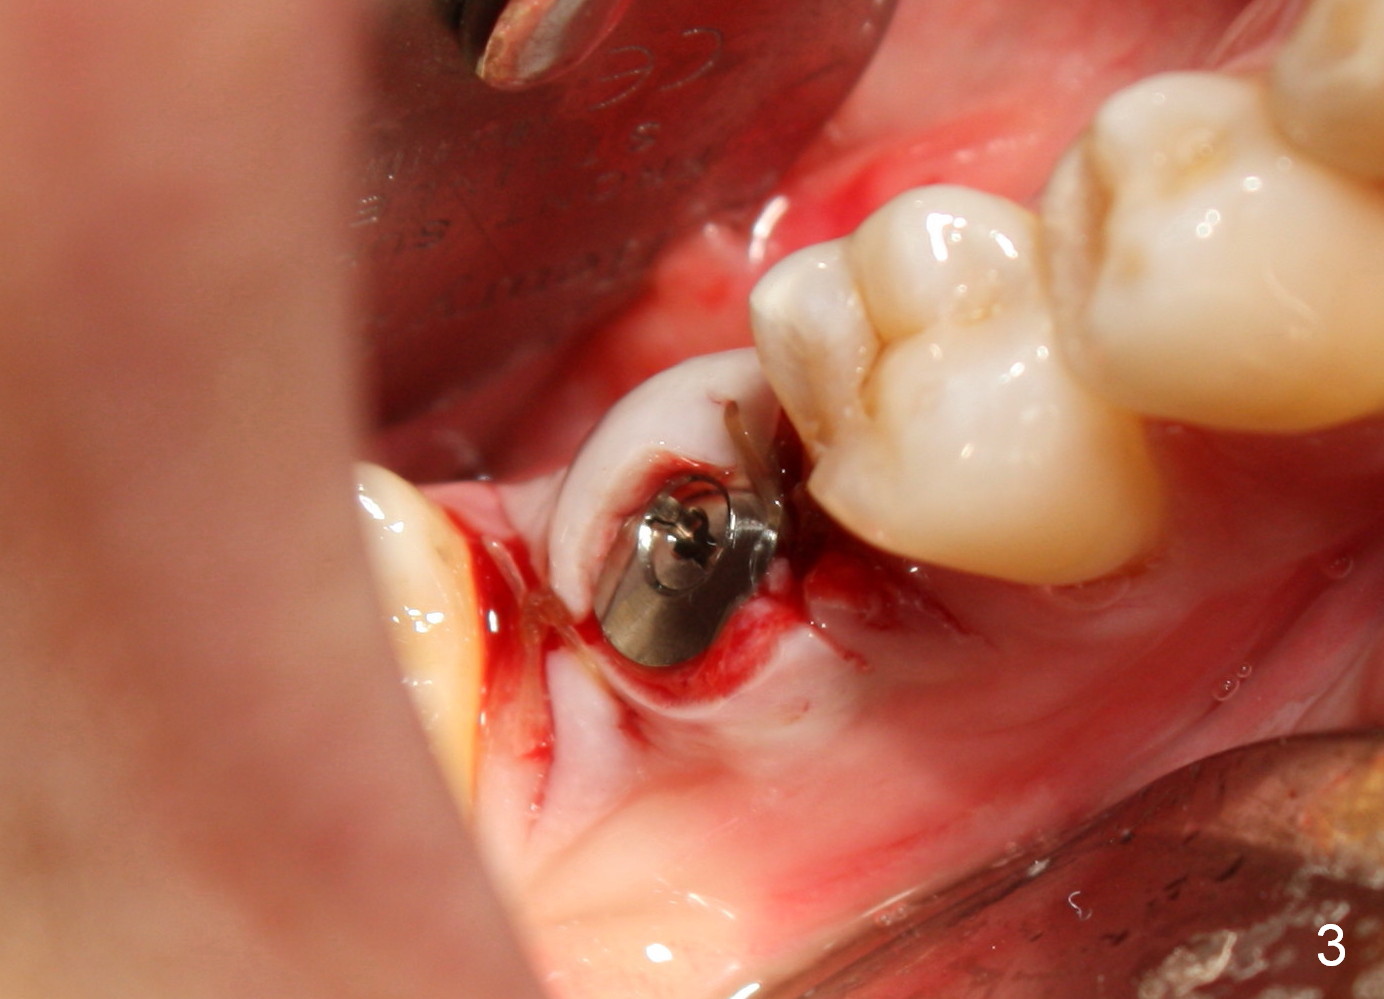

Six years ago, a 38-year-old patient presented to our office for new patient exam. She was scared of dentistry, but 3 of the third molars needed extraction. When the surgery was done painlessly, it was not too hard to persuade the patient to accept implant placement at the site of #30 (Fig.1; N: Inferior Alveolar Nerve). It was the 1st case when a 2nd implant system was adopted in the office. The implant is 3 mm shorter than the design (Fig.2). An incision was made for visibility (Fig.3). There is no bone loss 3.5 months postop (Fig.4). The crown is cemented 5 months postop (Fig.5); there is attached gingiva buccal to the implant. What surprised us the most is that she turns out to be one of the most faithful patients in our office. She never misses 6-month recall.